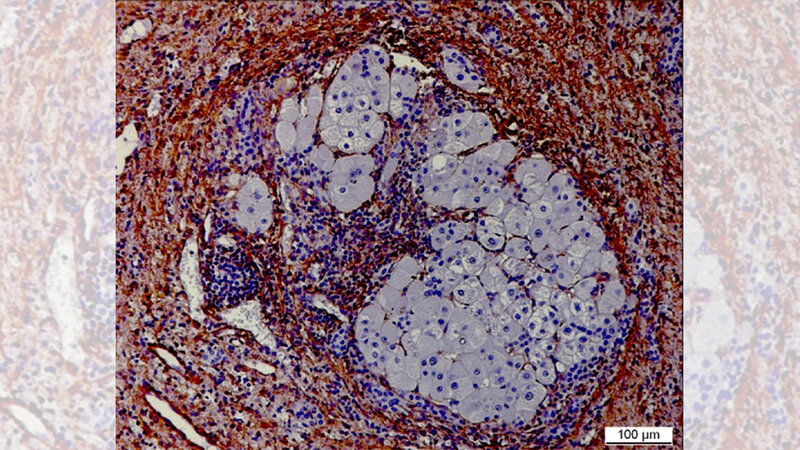

Untersuchung von zirrhotischen Knoten

Die Wissenschaftler untersuchen strukturelle Veränderungen der extrazellulären Matrix und der Zellinteraktion in sogenannten zirrhotischen Knoten, die als Kipppunkt (TIP) die Entstehung eines HCC begünstigen. Mittels sogenannter Cutting-Edge-Technologien analysieren die experimentellen Arbeitsgruppen die zirrhotischen Knoten in der Umgebung der Hepatozellulären Karzinome und vergleichen sie mit denen in den Lebern tumorfreier Zirrhotiker. Dabei untersuchen sie insbesondere die Matrixzusammensetzung und Veränderungen (fate changes) in den Makrophagen- und Fibroblasten-Zellpopulationen auf Biomarker, die den TIP der Progression zum Krebs charakterisieren.